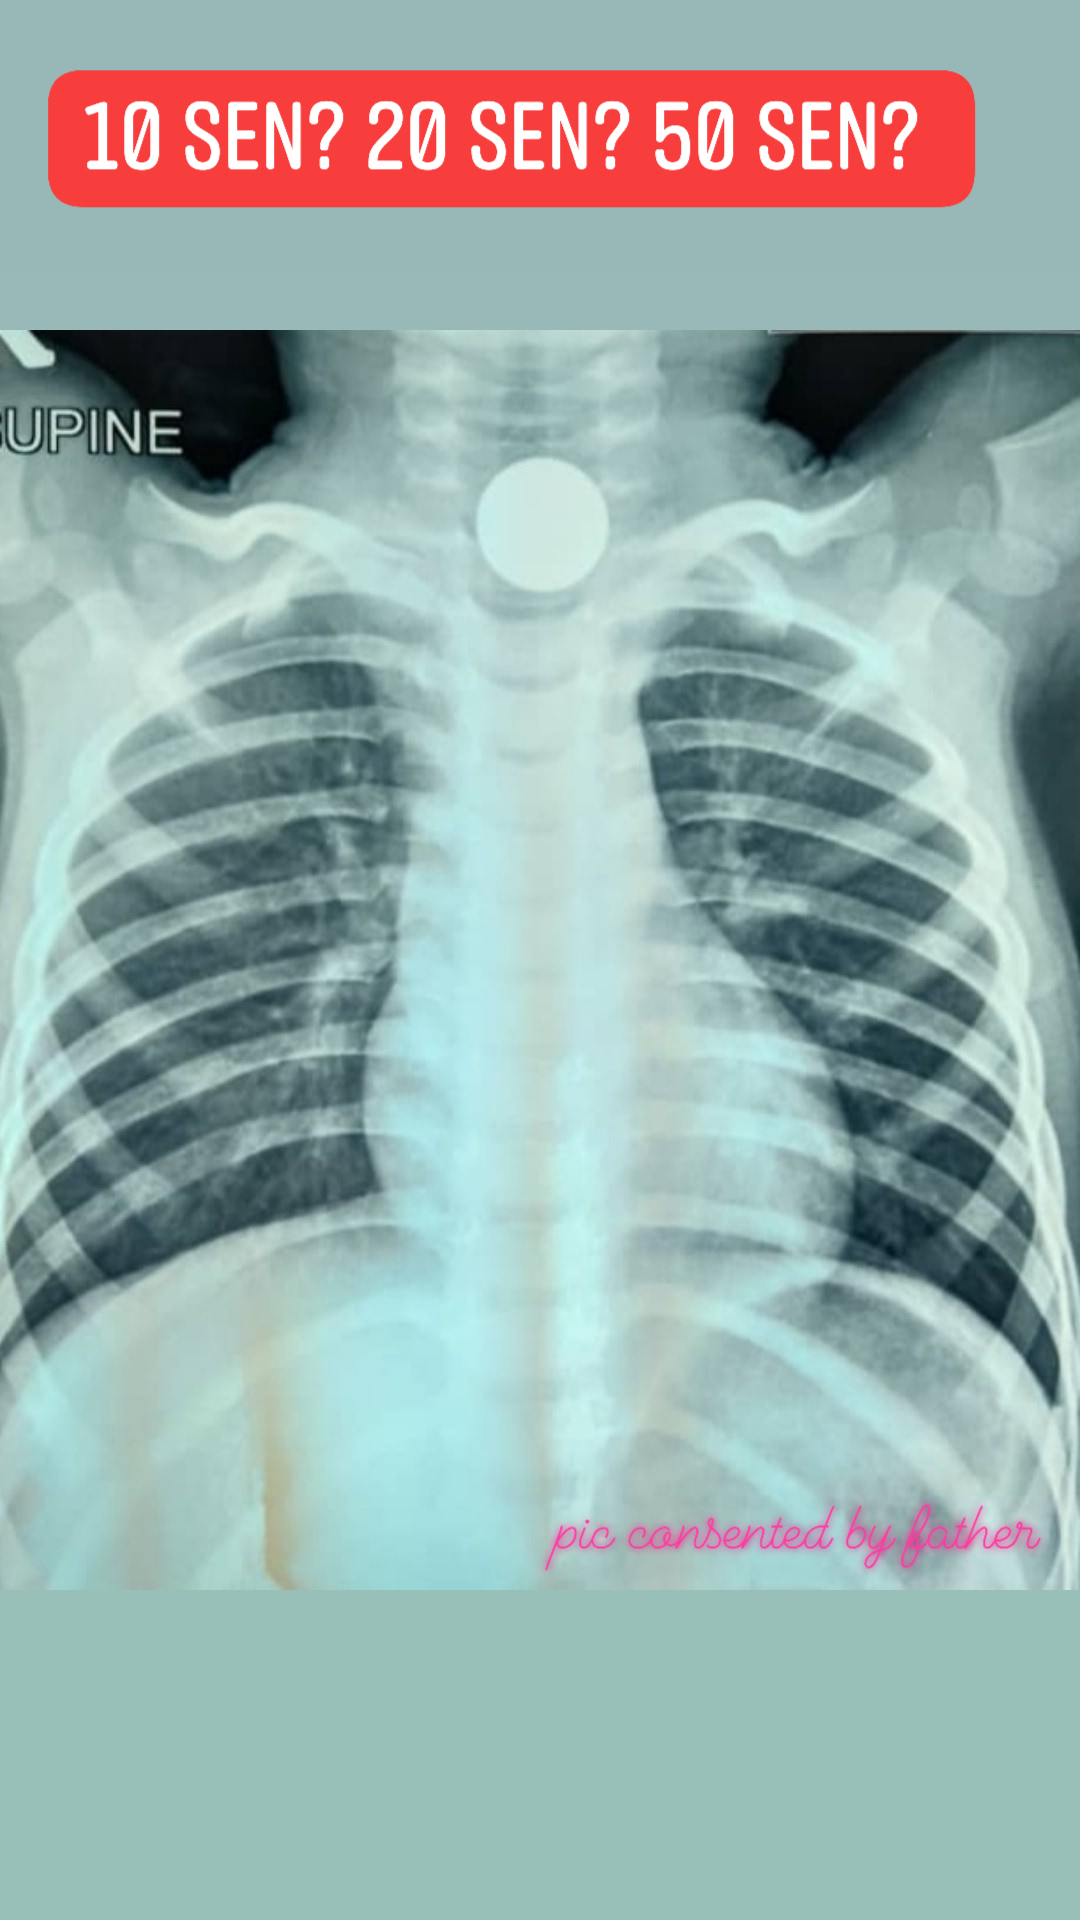

2岁童误吞20仙硬币险丧命 医生提醒:勿在幼儿前假装吞硬币

(八打灵再也1日讯)2岁幼童误吞一枚20仙硬币,卡在食道呕吐不止,所幸及时抢救才安全脱险。

在施以手术之前,沙依夫通过X光图看到硬币卡在幼童的食道中,可是他无法确定是10仙、20仙还是50仙的硬币。